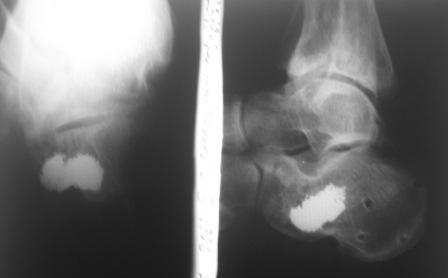

В качестве примера у себя нашёл снимки больного оперированного около двух лет назад, функция восстановлена полностью, ходит без каких бы то нибыло нарушений, сварщик - работает в полном объёме. Не сохранился первичный снимок, можете поверить на слово перелом примерно аналогичный, как у Вашего пациента.